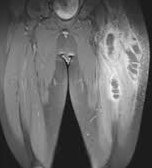

Pioneering achievement: curing blackwater fever

Albert Schweitzer was finally able to cure the dreaded

blackwater fever (destruction of red blood cells, e.g.

by high doses of quinine) by injecting 3% saline

solution under the skin of the thighs (letters from

Lambarene, p.575-576)